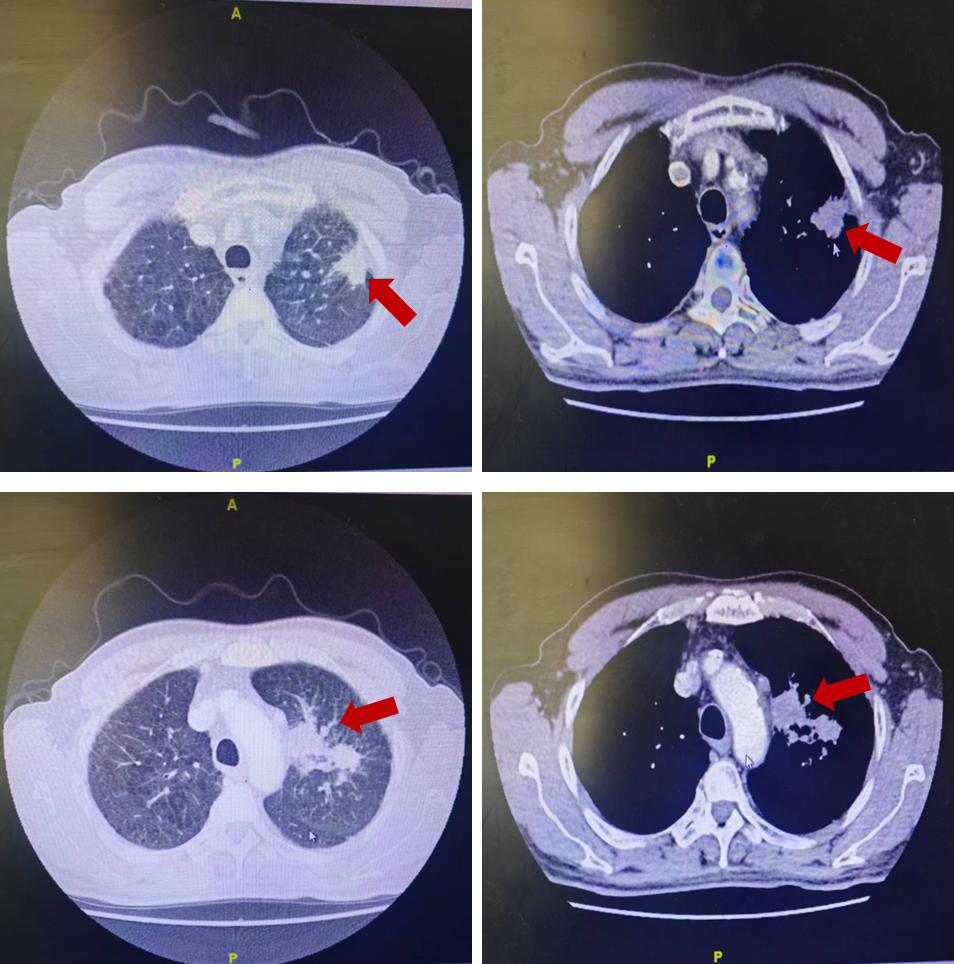

胸部增强CT:左肺上叶见两处肿物影,可见分叶、毛刺、胸膜凹陷征象,可见强化;纵隔内、左肺门区见增大淋巴结,部分融合。

该患者血CEA显著升高,淋巴结超声提示左侧锁骨上肿大淋巴结,胸部CT提示左肺上叶见两处肿物影,可见分叶、毛刺、胸膜凹陷征象,可见强化,纵隔内、左肺门区见增大淋巴结,部分融合,考虑肺部肿瘤可能性大。病理诊断是上述疾病鉴别的金标准,同时对于肿瘤的诊断需明确病理类型。请外科评估是否可行锁骨上淋巴结活检,行气管镜检查了解气道内情况,行PET-CT明确是否存在远处转移。